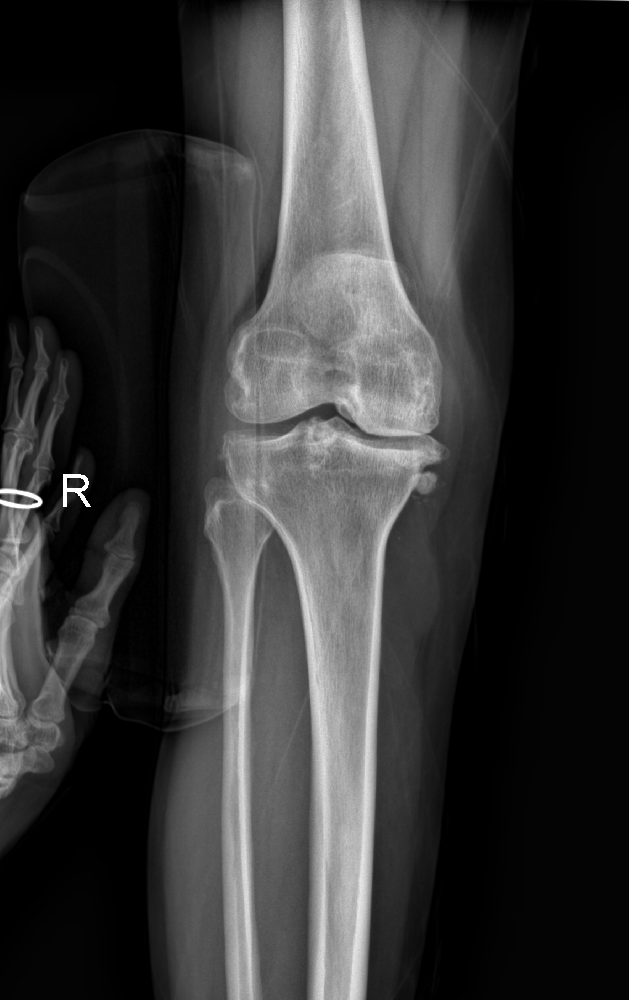

為了擺脫這長(zhǎng)期的苦痛,賈紀(jì)花選擇了市中區(qū)誠(chéng)德骨科醫(yī)院入院接受更為全面的檢查。在完成檢查后,醫(yī)生決定為她實(shí)施右膝關(guān)節(jié)內(nèi)側(cè)活動(dòng)平臺(tái)單髁置換術(shù)。手術(shù)完成后,賈紀(jì)花術(shù)后恢復(fù)良好,再次嘗到了疼痛消失的滋味。